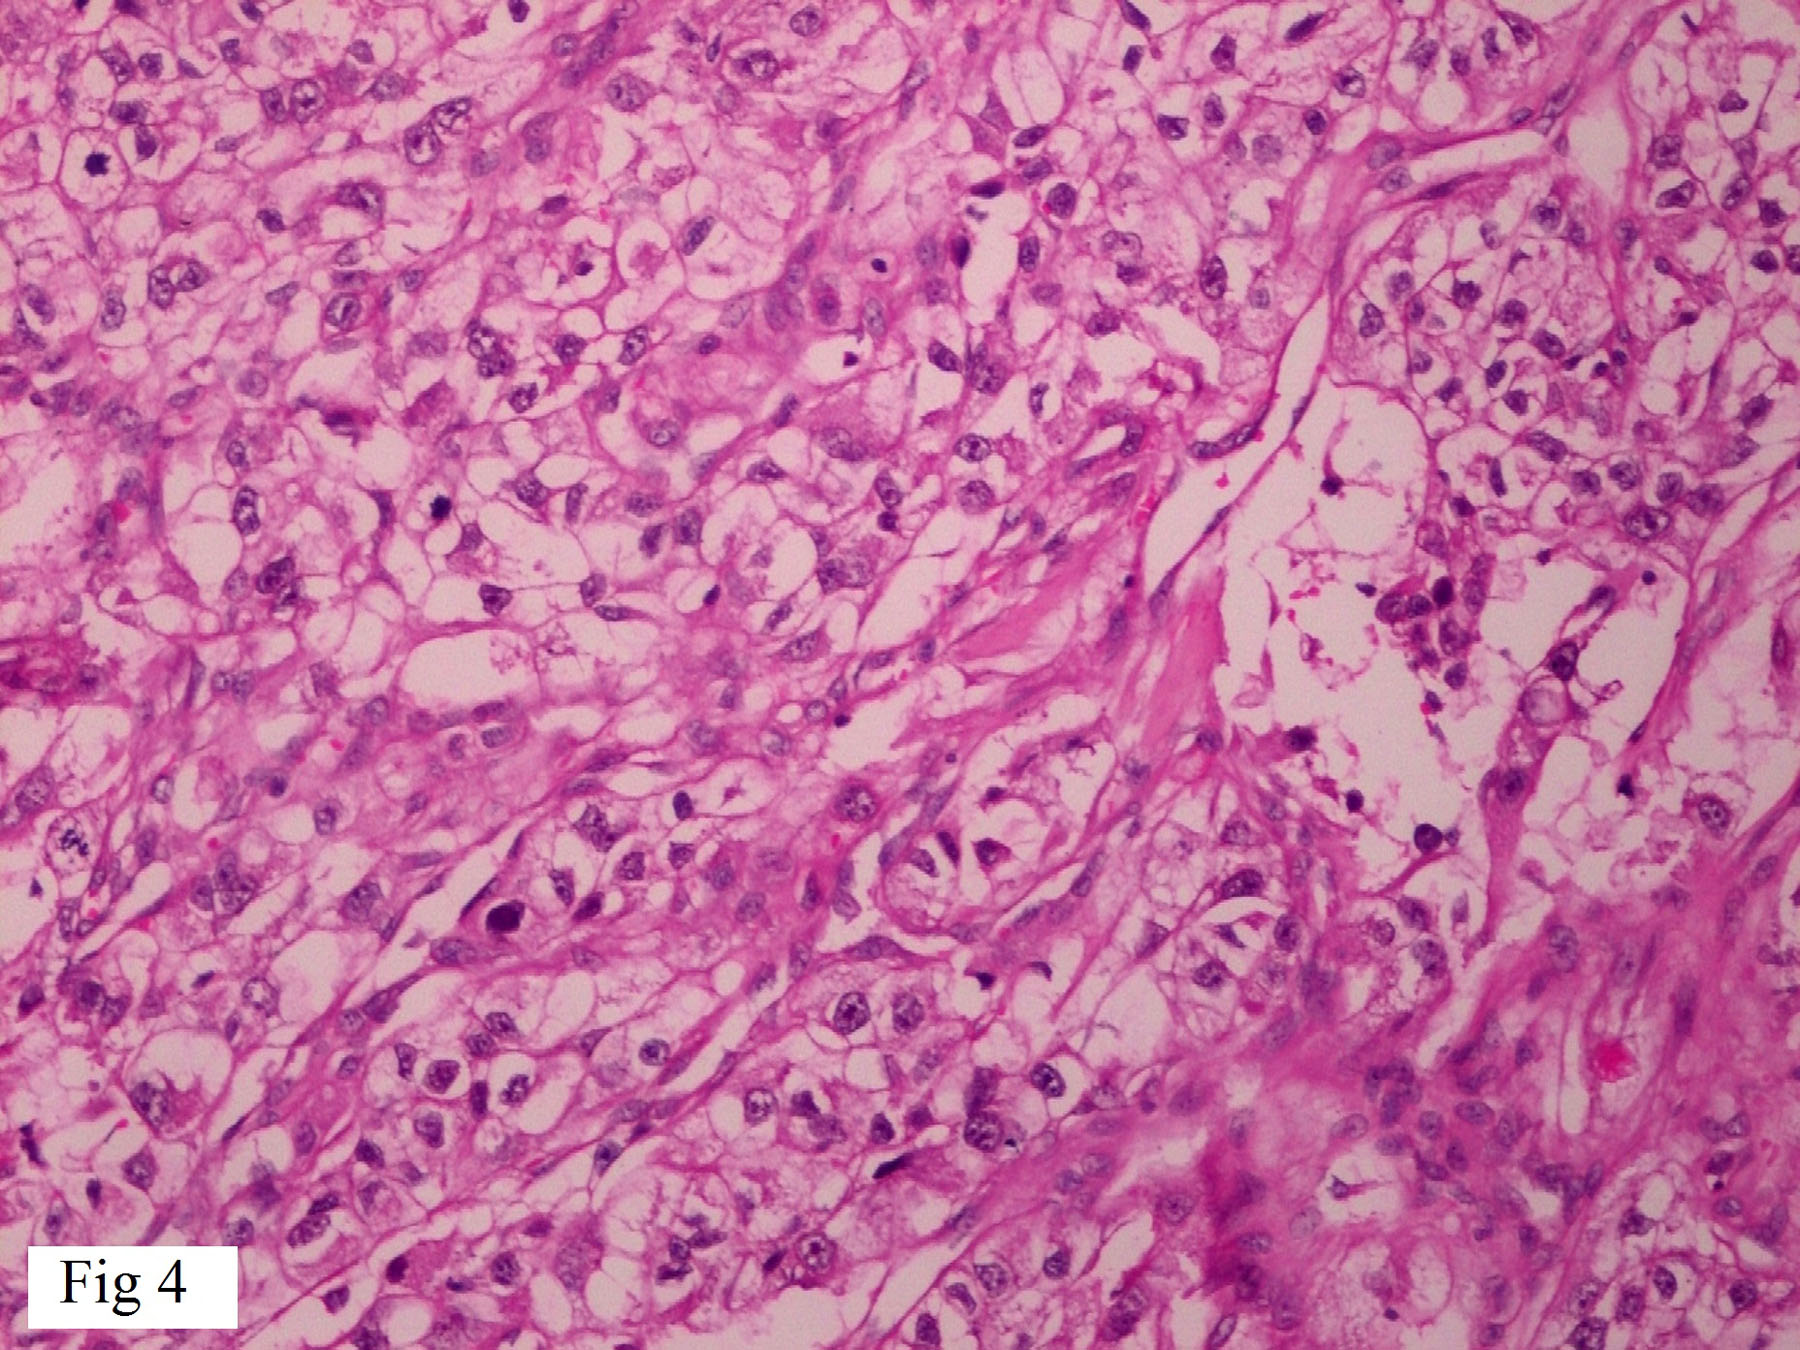

A 51-year-old male presented with a solitary, painless irregular swelling over chin for 3 months. On examination the swelling was firm, measuring about 3x2x1cm. No other significant past history was given at this point. Computed Tomography (CT) scan of face and neck showed a solitary well defined heterogenously enhancing mass arising from skin and subcutaneous tissue measuring 27x17x15mm in size. Radiological impression was of a primary skin tumour or metastatic tumour. FNAC was done and slides stained with May Grunwald Giemsa (MGG), Haematoxylin and Eosin (H&E) Papanicolaou (Pap) stain. Smears prepared from the swelling were moderately cellular and showed predominantly large singly scattered cells with few clusters of poorly cohesive cell. Cells showed an abundant pale, foamy/vacuolated cytoplasm with central to eccentric nucleus, 0-2 nucleoli and bland chromatin [Table/Fig-1]. In some cells, nuclei were totally or partially stripped of cytoplasm leaving bare nuclei [Table/Fig-2]. No intranuclear cytoplasmic inclusions were noted. Based on smear examination, a diagnosis of “clear cell malignant tumour, possibly metastatic RCC” was made. On second visit of patient detailed questioning was done with review of past records. History of nephrectomy 11 years back was elicited. Wide excision of tumour was done and sent for histopathology. On histopathological examination it was confirmed as metastatic RCC-clear cell type showing the typical clear cells arranged in solid sheets with a delicate branching vasculature [Table/Fig-3,4]. Immunohistochemistry for CK AE1/AE3 and CD10 was strongly and diffusely positive but was negative for S-100 and HMB 45.

Higher power view showing clear cells of RCC. [H&E 400X].